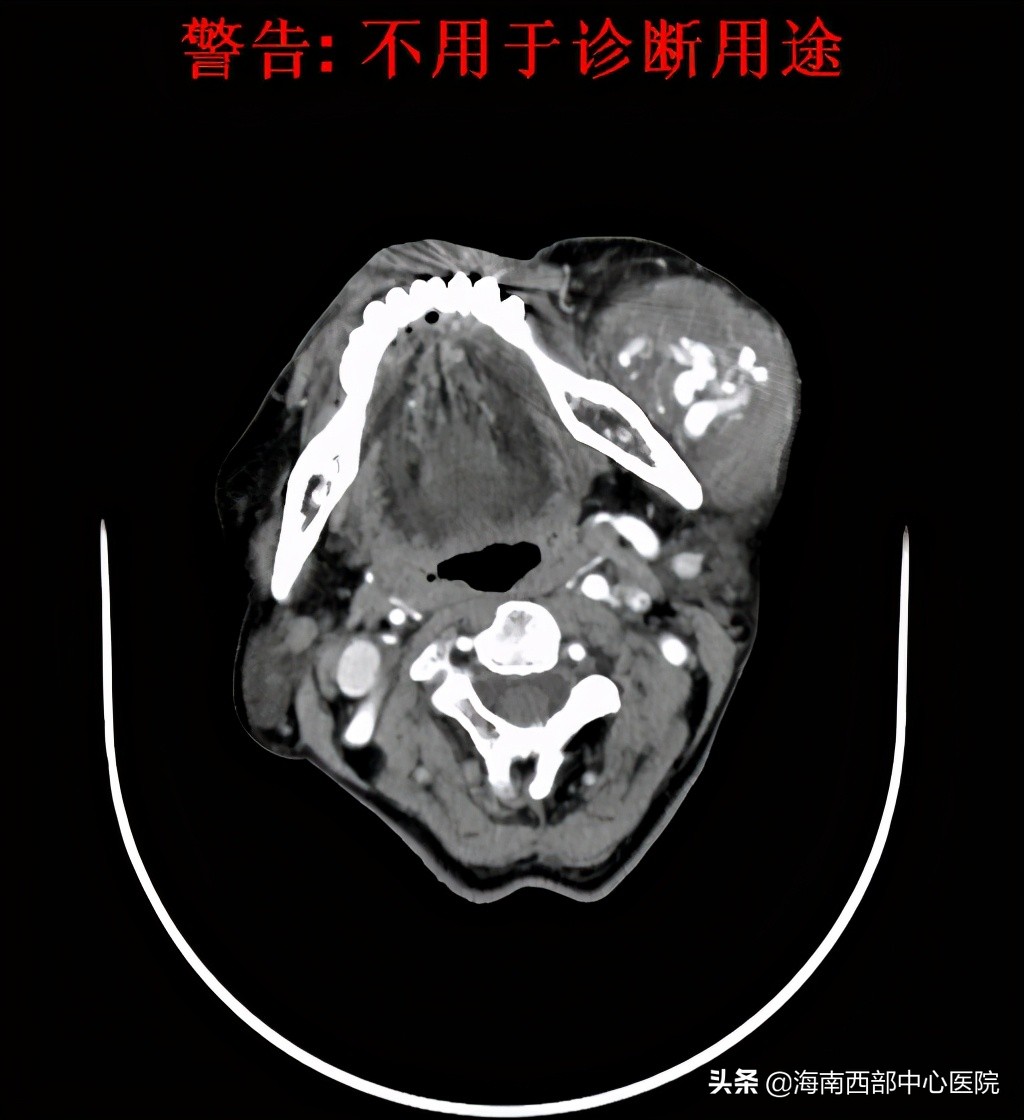

患者的信任,让西部中心医院的团队有了很大的信心,但患者复杂的病情不得不让参与手术的每一个医务人员变得谨慎细微。患者准确的诊断应该是间质为主的动静脉畸形,范围从颞部、颅底区域,到达咽旁、颌下区域,最大的风险就是周围血管全部扩张、增粗,术中在切除的时候会遇到非常多的像拇指一样的血管,稍有不慎,就会形成“喷射性”的快速失血,可以直接打到手术室天花板上,每次出血量都在200-300毫升,约占到人体总血量10%。而人体快速失血超过30%,就会引起严重的心脑血管问题,严重的可以导致死亡。尤其是头颈部,重要结构众多,到了动静脉畸形的深部,由于与周围的颅底区域的血管、神经和肌肉没有明确的界限,难以进行剥离,不可避免的会造成大量快速的出血。同时,这种疾病治疗的难点,就是在这个阶段,周围组织不停的出血,周围又有面神经、下颌骨等众多功能器官和颈动脉、颅底等重要结构,让外科医生不敢下手,但快速的失血又不给外科医生过多的迟疑机会。对于口腔颌面外科医生来说,动静脉畸形是最考验外科医生功力的疾病之一,对麻醉团队来说,由于快速的失血,血压的维持和多脏器循环的维护也是巨大的考验,是对医院外科实力的综合考验。

鉴于患者的病情,张院士在第一次面诊的时候就提出了“栓塞+切除”的综合治疗方案,这个治疗方法也是他的“独门绝活”之一,具有着丰富的治疗经验,通过颅面部软组织动静脉畸形的介入栓塞可栓塞缩小病灶,以利于手术切除。可降低病变的流速,控制并发症的发生以及作为手术前的辅助性栓塞。他的学生,现挂职于海南西部中心医院的杨溪副院长,按照多年来形成的治疗默契,有条不紊地组织着术前的准备工作,完善各类影像学检查。因患者病情复杂,手术难度大,在海南省属首例,该院张少明院长召集相关科室会诊,讨论术前备血、麻醉、术中栓塞及切除的细节,术后管理,甚至手术器械,都进行了一一的清点及准备。